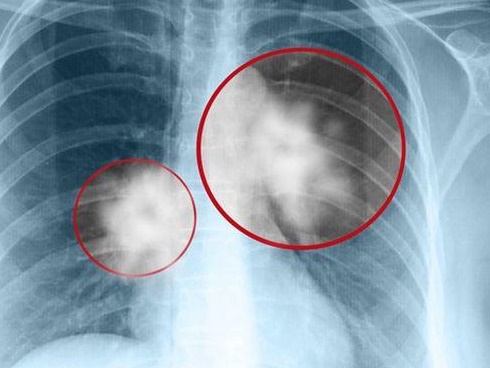

Ban đầu, người phụ nữ đi khám phụ khoa và nghi ngờ bị nhiễm trùng nấm mốc, nhưng không ngờ kết quả cuối cùng cho thấy cô bị ung thư nội mạc tử cung, chỉ có thể cắt bỏ tử cung mới có thể giữ mạng sống. Một thời gian sau, người mẹ lại tiếp tục đưa con gái đang học lớp 3 tới và nói rằng con gái đã có kinh nguyệt nhưng không biết cách thay băng vệ sinh nên đã bị viêm nhiễm phụ khoa.

Ngoài việc điều trị nhiễm trùng cho cả 2 mẹ con, bác sĩ Hong Yongxiang cũng cố gắng tìm hiểu lý do tại sao cả hai mẹ con liên tiếp gặp các vấn đề phụ khoa, mẹ bị ung thư nội mạc tử cung còn con gái lại dậy thì sớm. Sau khi kiểm tra thêm, bác sĩ Hong Yongxiang phát hiện cả 2 mẹ con có nồng độ formate cao gấp 3-5 lần so với bình thường, chứng tỏ thường xuyên tiếp xúc với chất này tại gia đình.

Wu Xinjie, một bác sĩ y khoa của Đại học Y North Union, đã từng chỉ ra rằng chất hóa dẻo có thể gây ảnh hưởng tới nội tiết tố nữ. Tiếp xúc lâu dài có thể làm tăng nguy cơ ung thư vú và ung thư nội mạc tử cung ở phụ nữ mang thai. Nồng độ chất chuyển hóa càng cao, nguy cơ bất thường bẩm sinh ở cơ quan sinh sản của các bé trai càng cao.